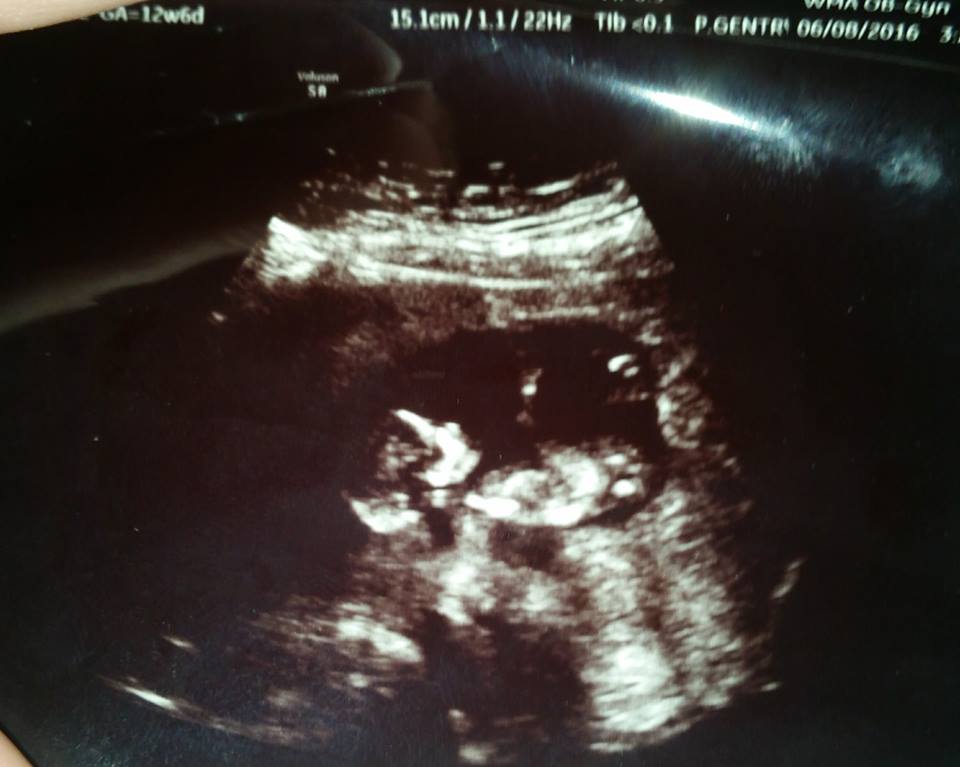

The ultrasound tech didn't say which she thought but this is clearly a boy to me, is there ANY chance it could be a girl? I'm happy either way but after 2 boys, I was hoping for a little girl!Attachment 31976

potty shots are not reliable at 12 weeks. Did you get a nub?

No, the ultrasound tech acted like I was stupid when I asked and I've been so hormonal, I just didn't want to deal with it.. I started to explain and she gave me a potty shot so I just shut up. I THOUGHT I saw it for a split second during the scan abut I couldn't really tell. I have a side profile shot, but I can't see the nub. Baby's bottom half is hard to see in it, it all looks dodgy. Posting it anyway.